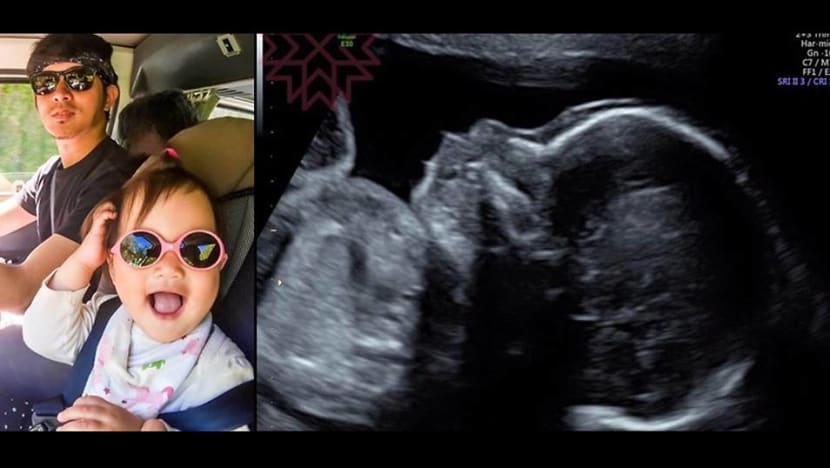

The actor shared ultrasounds photos of his unborn son

Taiwanese actor Chris Wang took to Facebook on Saturday (Mar 4) to announce that his wife is currently five months pregnant with their second child, a baby boy, after months of maybe-baby speculation from the media. The post was also accompanied by several ultrasound snaps of his unborn child. He wrote in his post, “Our child is very healthy; we will cherish everything that we have and share the joy with everyone”.